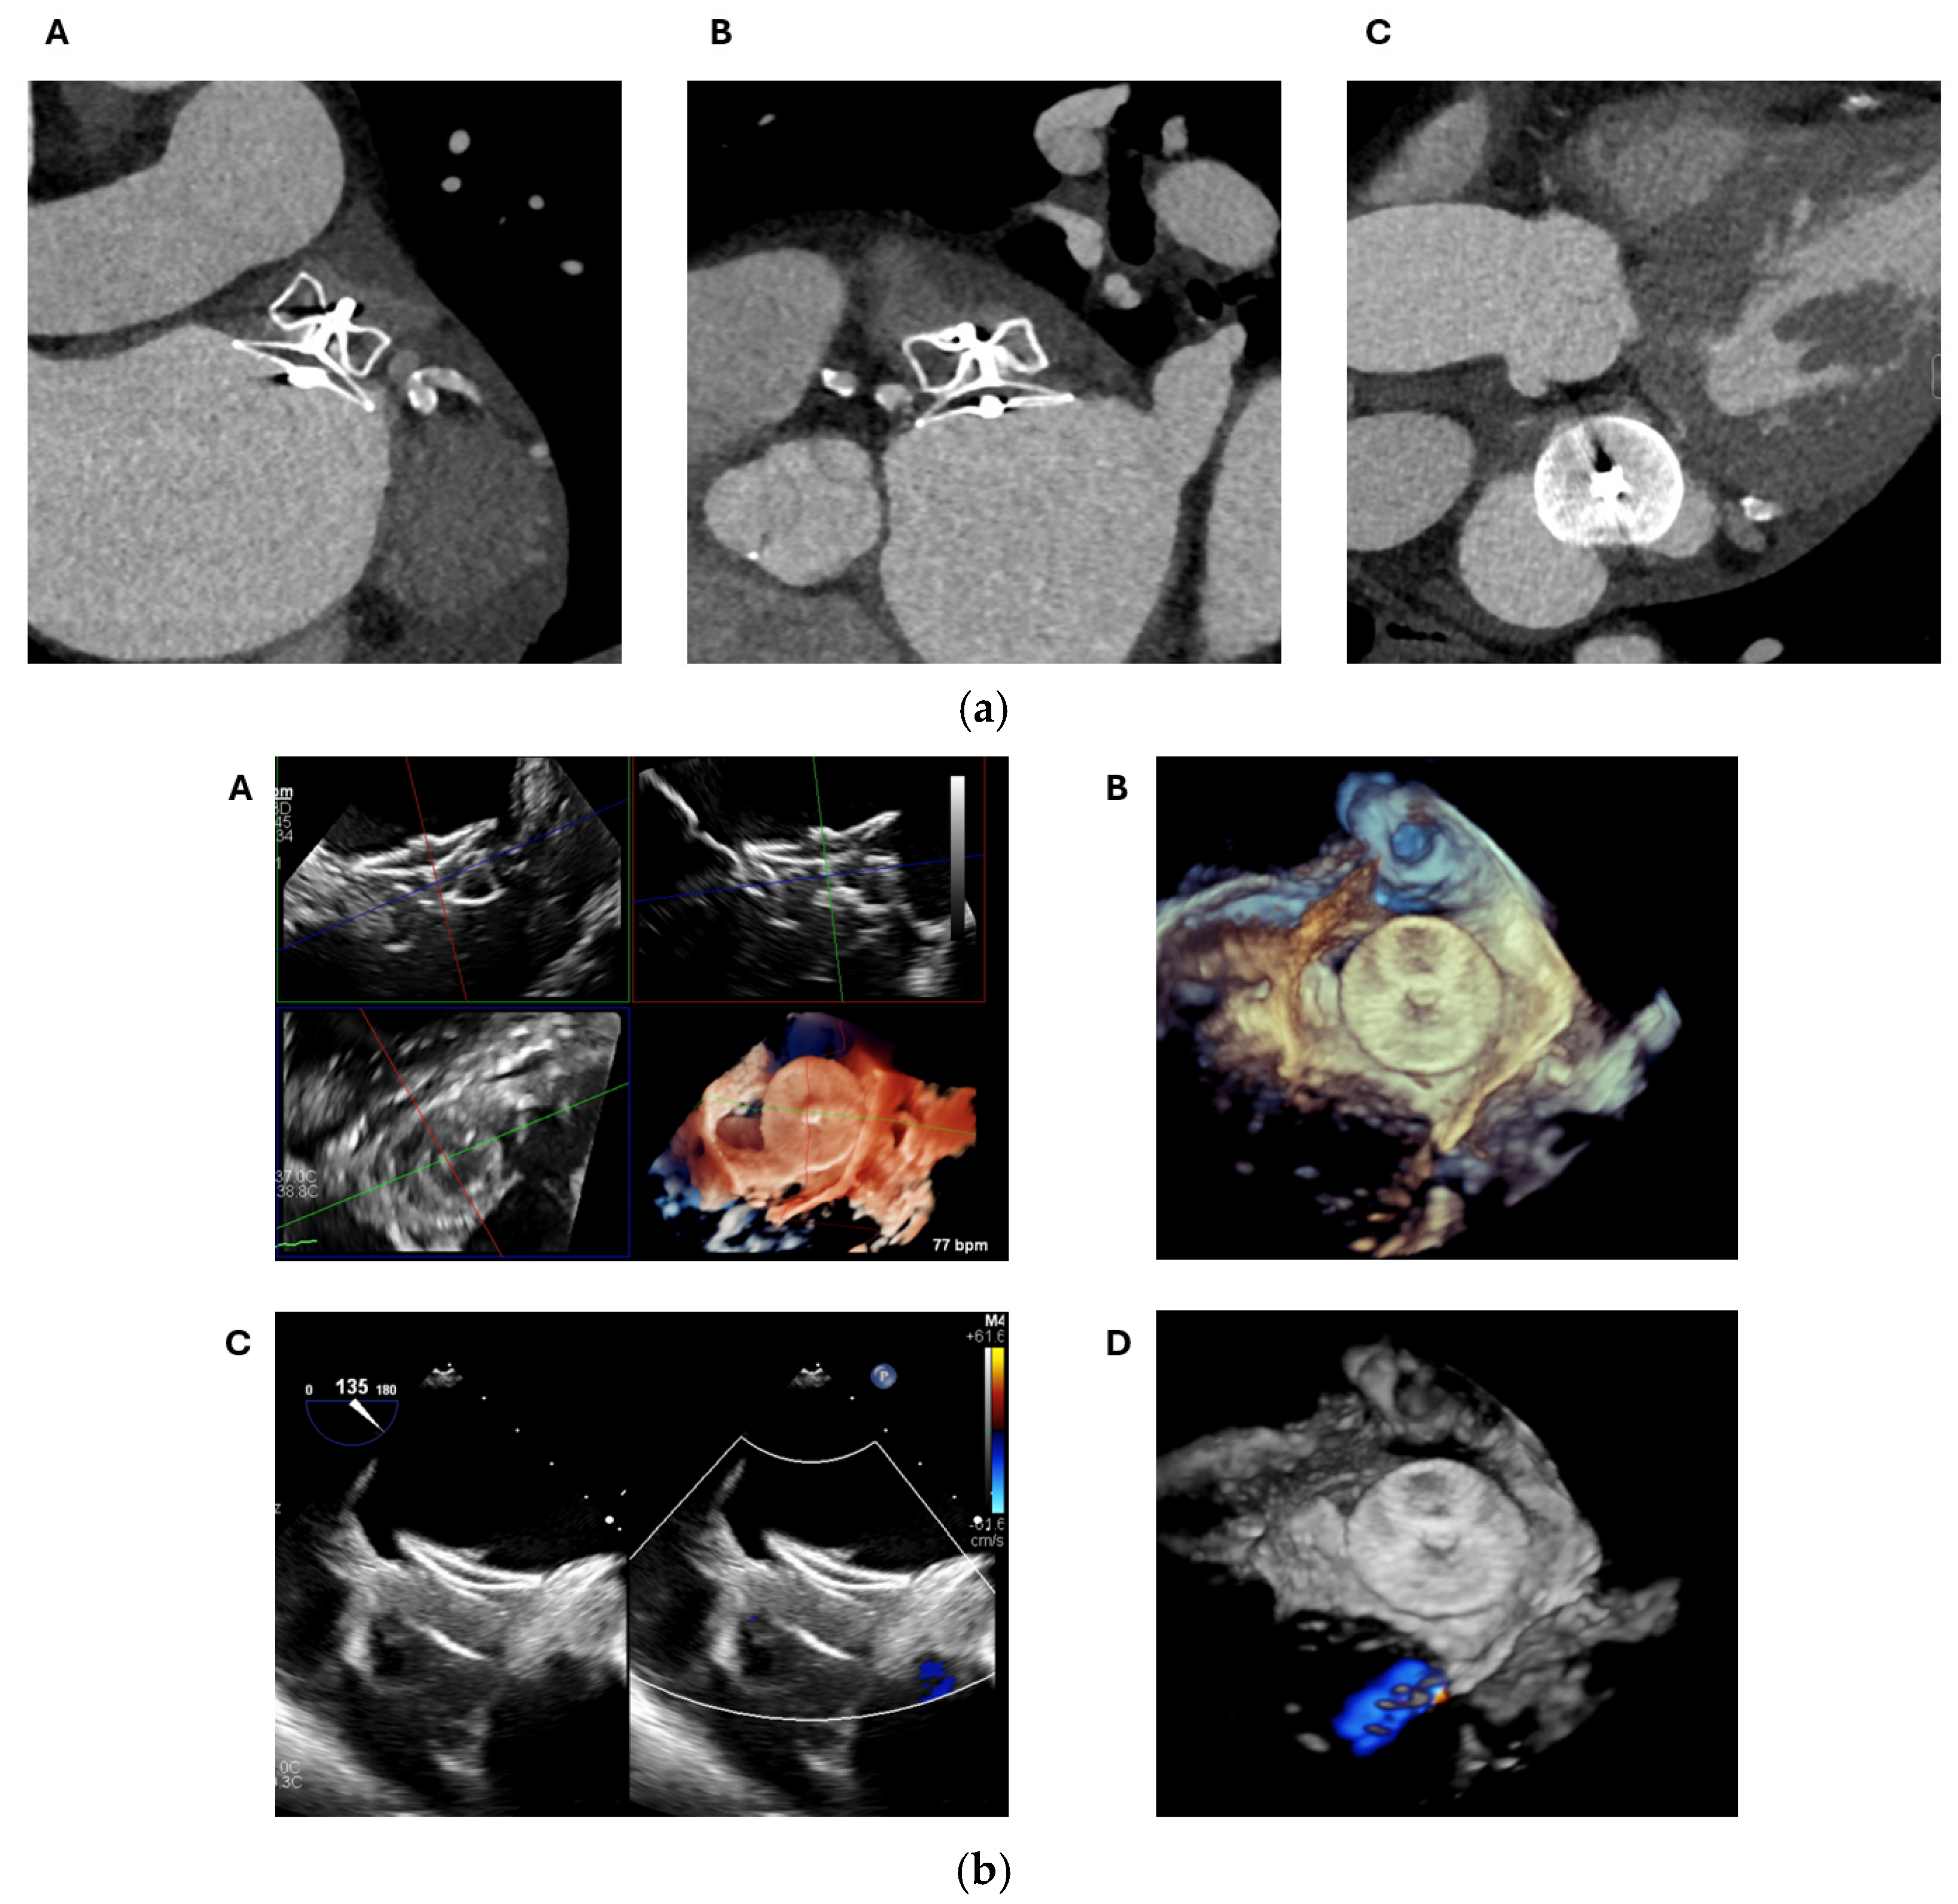

2.1. Cardiac CT

2.1.1. Anatomical Contraindications

2.2. Transoesophageal Echocardiography

2.2.1. LAA Thrombus Assessment

2.2.2. LAA Measurements (Anatomy and Morphology)

2.2.3. Intra-Procedural TOE